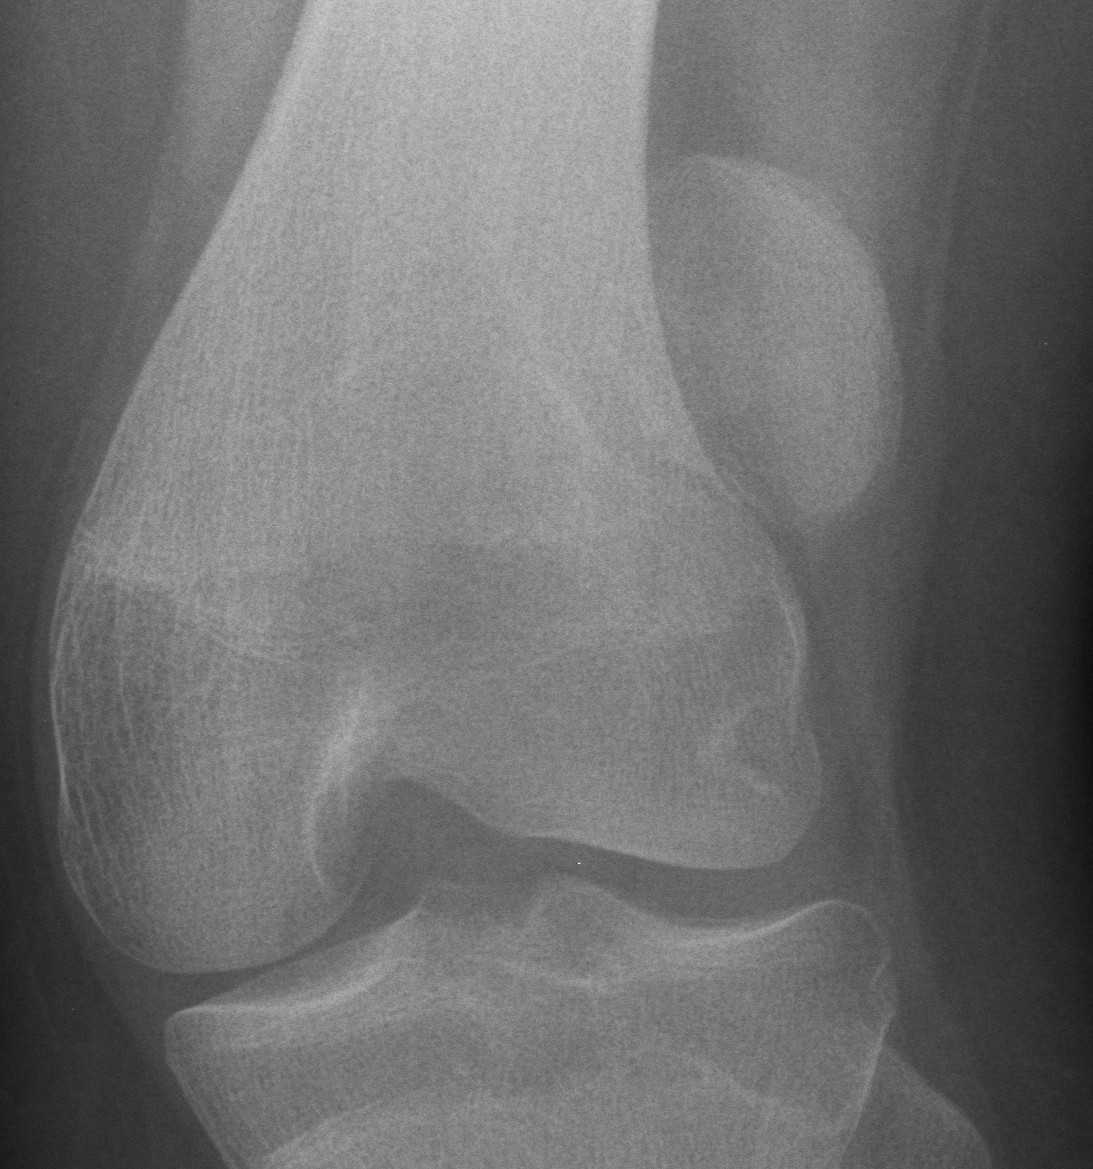

Repeated dislocation of patella with minimal trauma

- 15-20% of paediatric acute patella dislocations

- more common girls

- often bilateral

Dislocation occurs unexpectedly when quadriceps contracted with knee in flexion